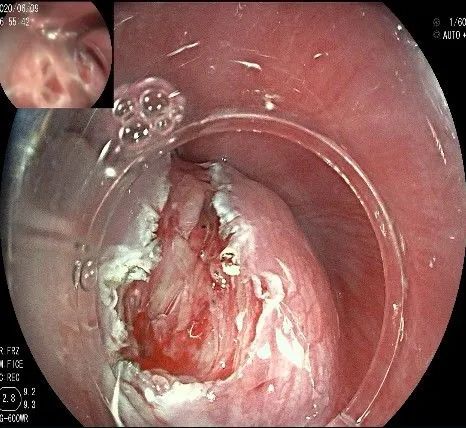

在食管腔内,瘤体的两侧行粘膜下注射后,在瘤体顶部纵向自口侧向肛侧切开食管粘膜。

向下一直切开至齿状线处,白色为鳞状上皮,红色为腺上皮,颗粒样的部分,就是炎性息肉。切开后可见瘤体为白色,表面有血管网,质地较韧。

沿切开的边缘,从口侧开始向下进行粘膜下剥离,剥离的间隙是瘤体之上粘膜之下,期间反复进行粘膜下注射。